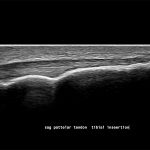

Imagini clinice:

Aplicatii: